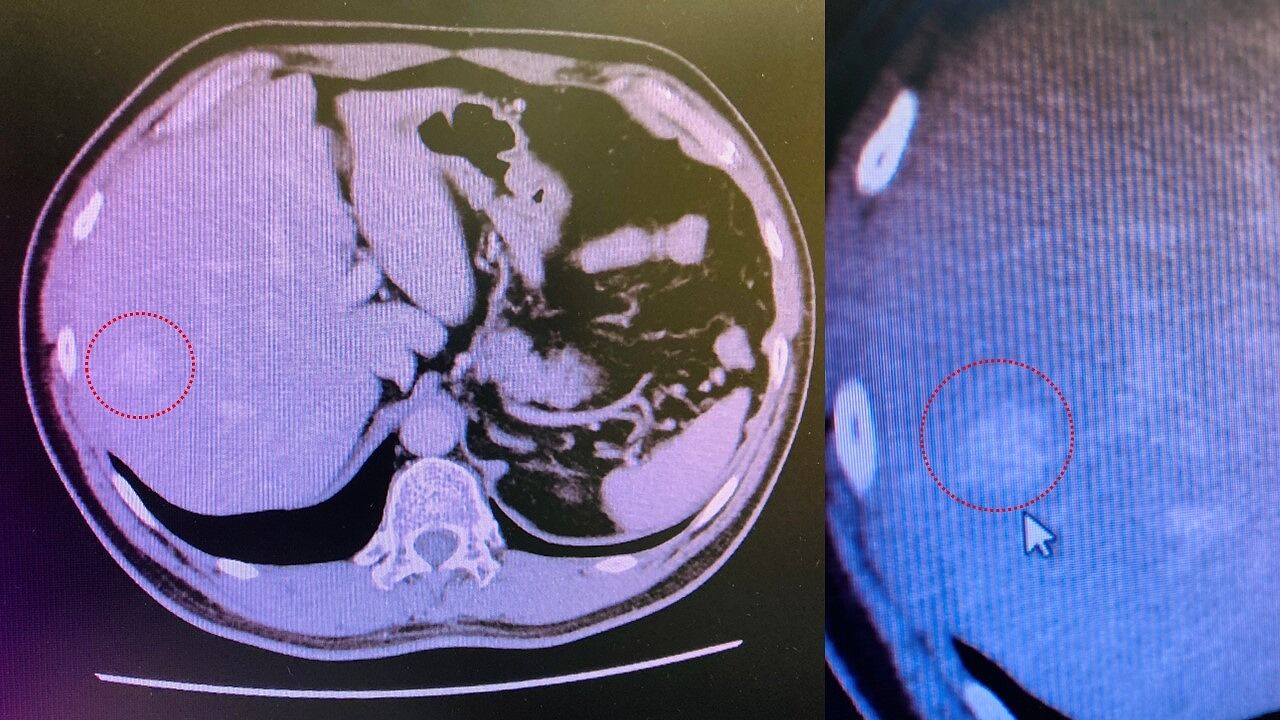

満面の笑みで人間ドック!・・・だったのだが

人間ドック再検査。若干、シリアス・・・。

再検査で「ガンではない!」と断定!

一安心して満面の笑み♪